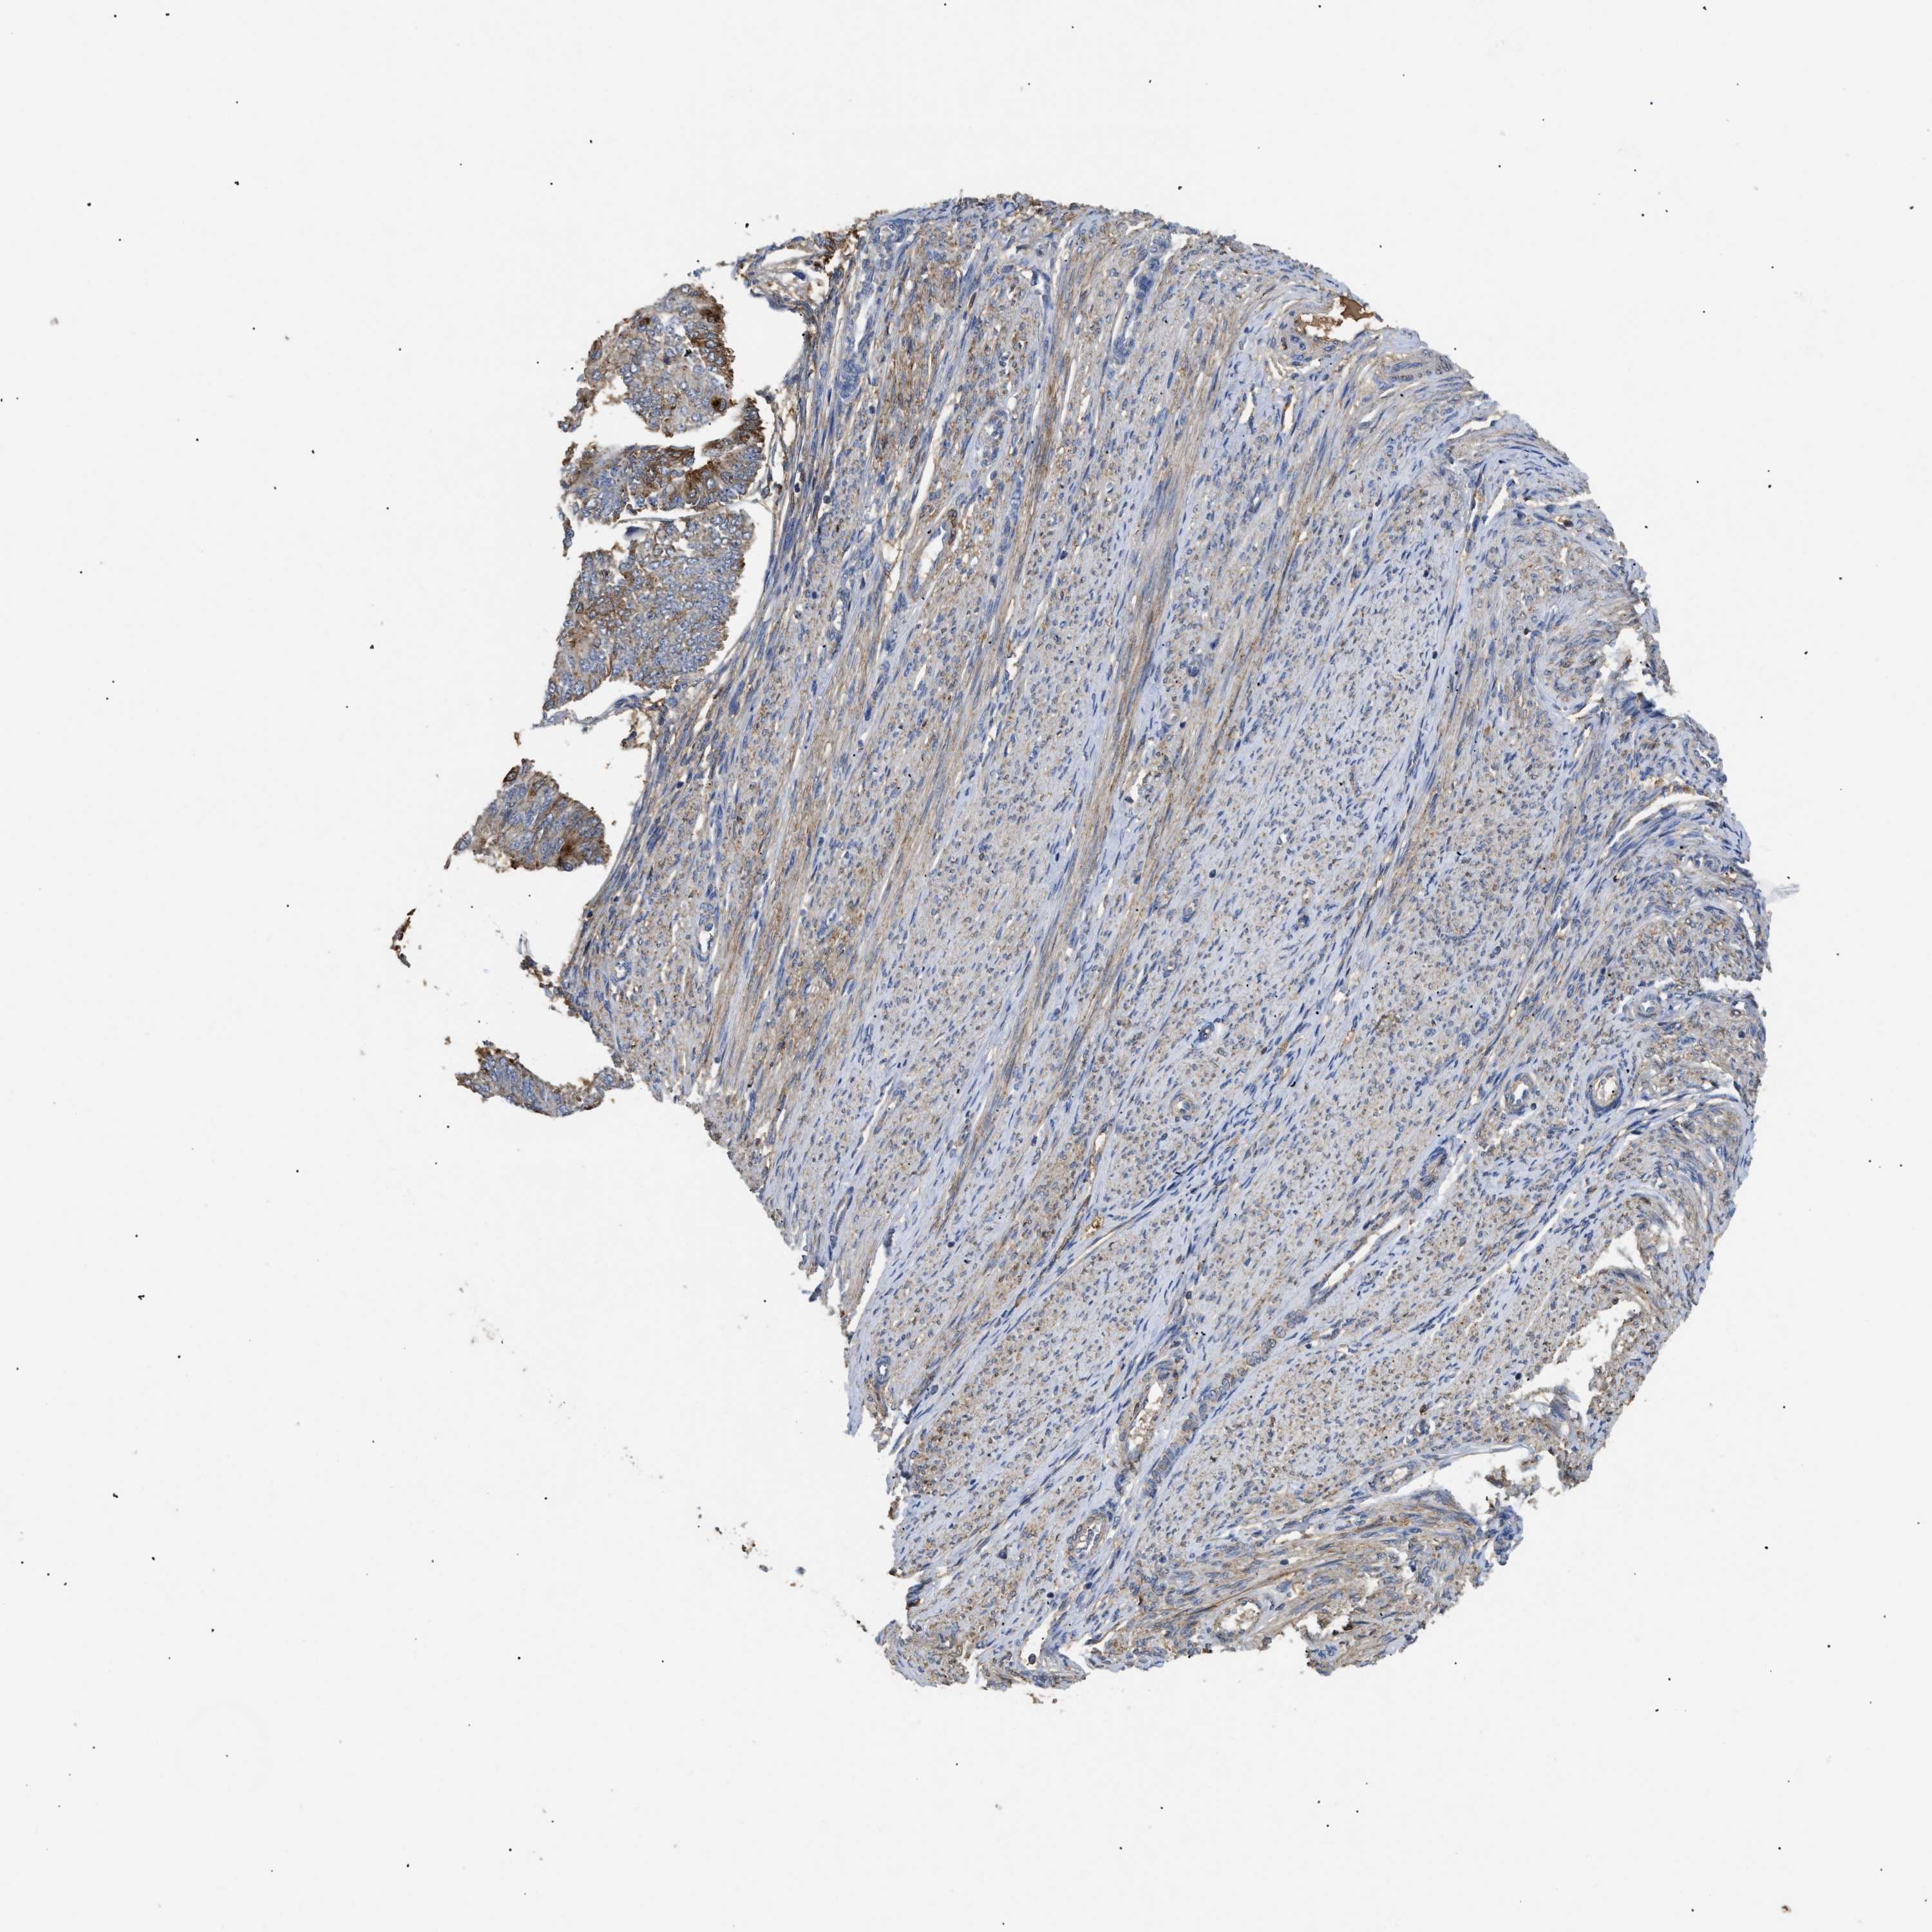

ENDOMETRIAL CANCER - Protein expressioni

A mouse-over function shows sample information and annotation data. Click on an image to view it in a full screen mode. Samples can be filtered based on level of antibody staining by selecting one or several of the following categories: high, medium, low and not detected. The assay and annotation is described here.

Note that samples used for immunohistochemistry by the Human Protein Atlas do not correspond to samples in the TCGA dataset.

Antibody stainingi

Antibody staining in the annotated cell types in the current human tissue is reported as not detected, low, medium, or high, based on conventional immunohistochemistry profiling in selected tissues. This score is based on the combination of the staining intensity and fraction of stained cells.

Each image is clickable and will lead to virtual microscopy that enables deeper exploration of all samples and also displays staining intensity scores, fraction scores and subcellular localization as well as patient and tissue information for each sample.